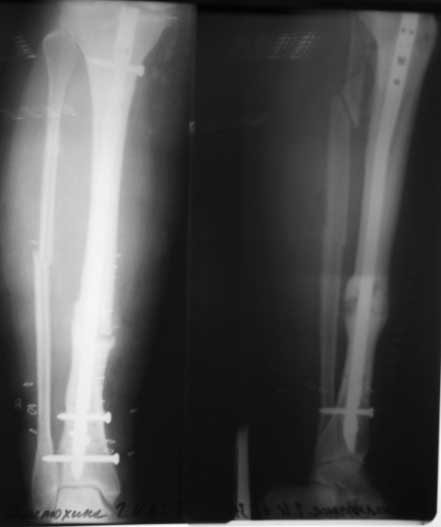

Большое спасибо за советы! Сегодня прооперировал больную. Все дистальные винты были сломаны, но они легко удалились, сломанные концы просто выбивал на противоположную сторону (использовал для этого обломок старого сверла 3,2)и через проколы вынимал.Попытался удалить гвоздь целиком с помощью спицы с оливой, но она не пропустила запирающую спицу до дистального обломка стержня. Помучился. Пришлось удалять по частям,проксимальный экстрактором,открыл зону ложного сустава, вынул промежуточный фрагмент иглодержателем, а вот дистальный обломок стержня уже получилось удалить с помощью спицы с оливой, но заклинивал её кистевой спицей. Ещё раз большое спасибо всем за участие!

Имя     : жПФП497.jpg